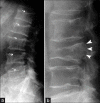

Musculoskeletal disorders are among the most common problems affecting the elderly. The resulting loss of mobility and physical independence can be particularly devastating in this population. The aim of this article is to present some of the most frequent musculoskeletal disorders of the elderly, such as fractures, osteoporosis, osteoarthritis, microcrystal disorders, infections, and tumors.